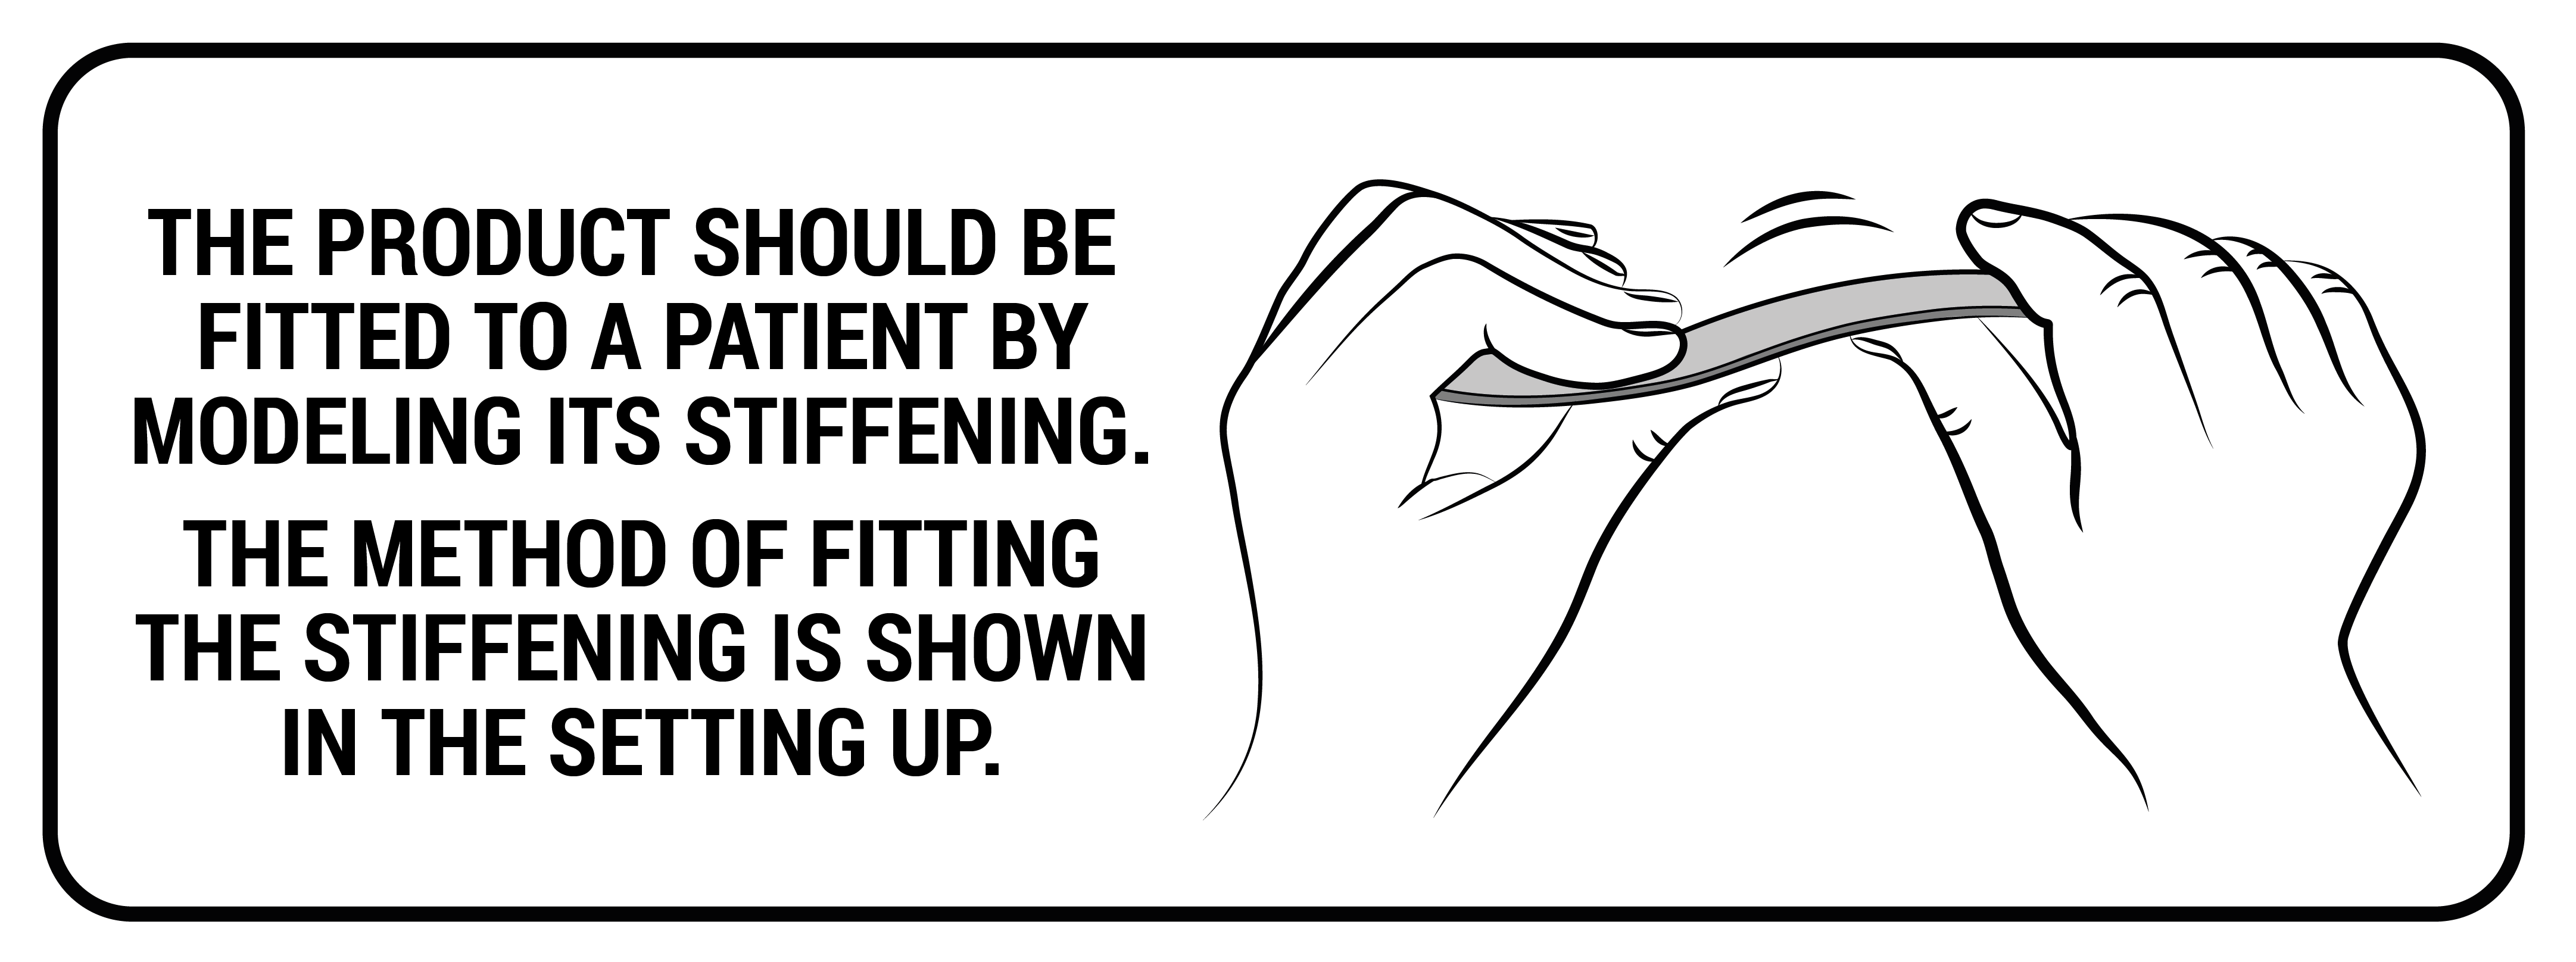

Our kids immobilizer AM-TUD-KD is equipped with 3 aluminium stays which are anatomic-shaped and maintain knee joint in extension. 4 circumferential straps allows to adjust required compression, according to therapeutic needs. The fabric is easy to attach and provides wide range of circumferential adjustment.